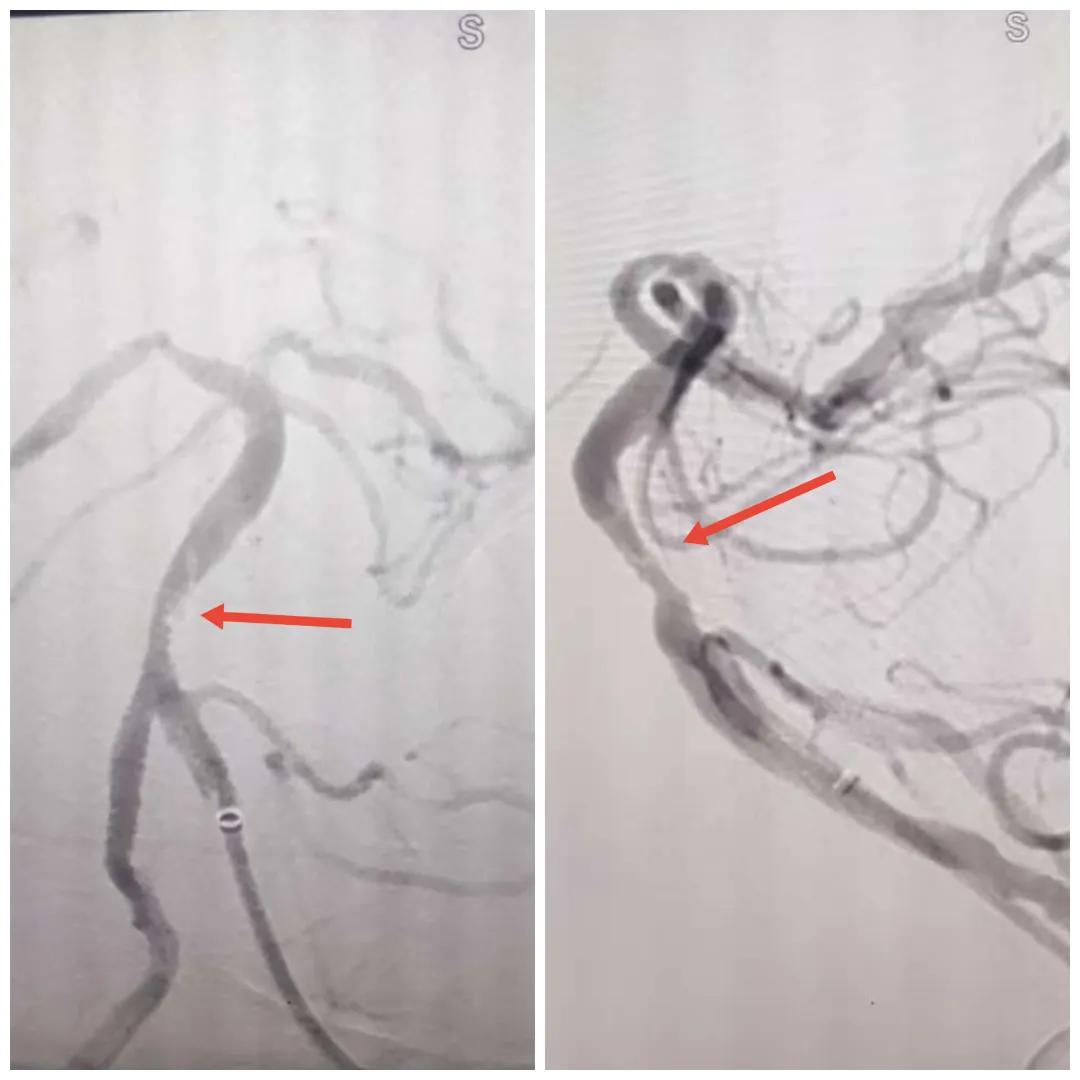

在經(jīng)造影后,主刀醫(yī)生腦一科副主任楊慶堂發(fā)現(xiàn)患者基底動脈下段重度狹窄且狹窄段以遠(yuǎn)有大負(fù)荷血栓,其狹窄處考慮為動脈夾層,手術(shù)難度及風(fēng)險較大。楊慶堂副主任在彭壯副主任醫(yī)師的協(xié)助下運用spaceman(太空人)技術(shù),中間導(dǎo)管抵近血栓抽吸配合支架拉栓,成功開通血管。再次造影可見基底動脈管腔明顯增寬,遠(yuǎn)端血管顯影良好,且等待20分鐘后造影仍顯示血流通暢。楊慶堂副主任考慮到本次手術(shù)時間不宜過長,現(xiàn)患者基底動脈及分支前向血流維持良好,給予其抗栓藥物應(yīng)用后結(jié)束手術(shù),并建議患者3個月后復(fù)查造影,明確其基底動脈夾層情況。

造影可見血管夾層和大量血栓形成

取栓后血管管腔增寬,前向血流良好